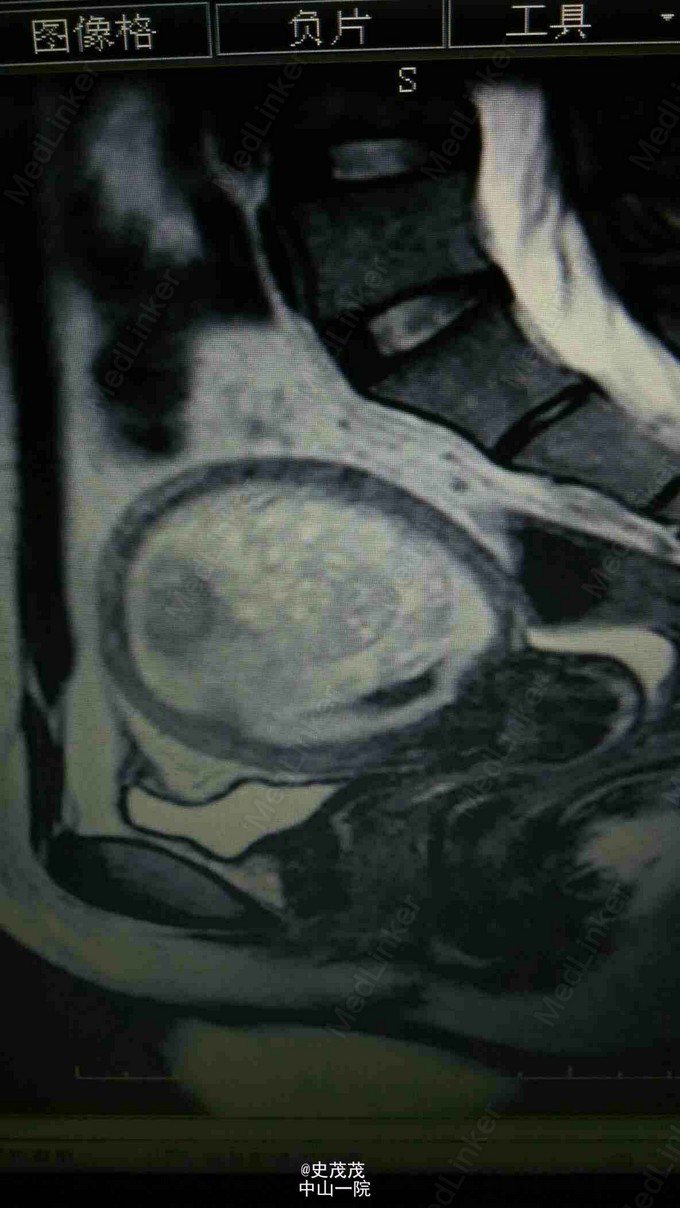

患者,女,21岁。因“停经2月,下腹痛伴阴道流血1天”入院。 患者平素月经规律,3年前顺便1胎。LMP:2014-11-08,1天前无明显诱因出现下腹隐痛,伴阴道流血,量少,色鲜红,无伴组织物排出。 我院院HCG 133146.2 IU/L, B超示:宫内见较强回声,大小约48×45mm,边界欠清,内见不规则液性暗区,其前方见低回声环绕,深约6mm。不排除滋养细胞肿瘤可能。 盆腔MR提示:子宫腔明显扩大,内巨大不规则肿块影,呈长T1、长T2信号,信号不均匀,T1W1可见较多片状偏高信号,病变侵入子宫浅肌层,子宫肌层受压变薄,信号不均匀,增强扫描肿块明显不均匀强化。子宫左侧侧壁见一结节影,大小约2.6×2.3cm,增强扫描病灶强化较肌层稍差。子宫直肠陷凹少量积液。诊断提示:考虑滋养细胞肿瘤可能伴宫腔内出血,肌层轻度受侵犯;子宫左侧壁肌瘤可能。 既往史、个人史、婚育史、家族史无特殊。 1月10号至1月17号予5FU+Act-D一程化疗 复查 HCG 1月13号 349810IU/L 14号 333780IU/L 16号 282090IU/L B超示子宫宫腔内见范围92×58mm混合回声,外侧肌层菲薄。 19号复查 HCG 197821IU/L 化疗过程顺利无腹痛及阴道出血,予出院,嘱3天后复查HCG,3周后复治。 这个病例看似很平静,其实暗藏危险。这里的医保,最开始打算回家乡治疗。主任多次向其强调子宫大,肌层薄,还会再增大,随时有子宫破裂大出血可能,患者终于同意在此化疗一疗程,再回家治疗。上化疗后,HCG并没有及时下降,子宫也不减小反而增大,虽然大家都认为是化疗药物起作用需要时间,但谁又能承担效果不好子宫继续增大的风险呢。主任仔细询问化疗药物的使用剂量,并向患者强调尽量卧床休息,减少活动,并嘱密切注意患者腹痛,阴道流血情况。另外,患者拒绝做胸部CT说回家再作。 后续的治疗我应该不会知道了。